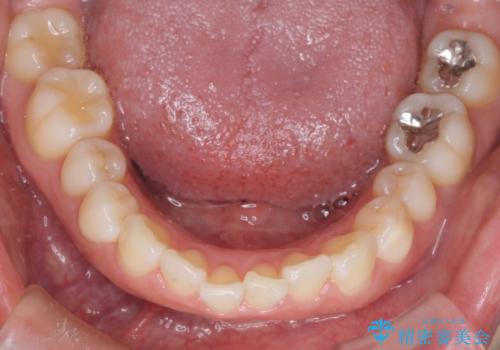

- 上下前歯のがたつきを主訴に来院されました。

抜歯を行い、前歯のがたつき、前歯の出ているところを改善できました。

患者様の満足感も高く治療を終えられました。